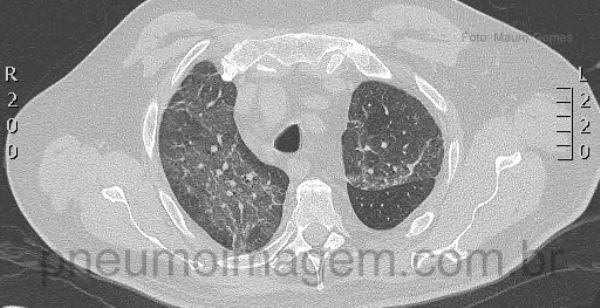

Cortes tomográficos em lobos superiores, na altura da carina e nos lobos inferiores demonstrando opacidades em vidro fosco difusas bilaterais.

Tomographic slices in the upper lobes, in the carina level and lower lobes demonstrating bilateral diffuse ground glass opacities.

Como se pode notar nesse caso de PAC, predominam as opacidades em vidro fosco e intersticiais, diferentes do padrão clássico de consolidação lobar geralmente descrito para o pneumococo.

As noted in this patient predominate ground glass and interstitial opacities, different from the classical pattern of lobar consolidation generally described for pneumococcal disease.